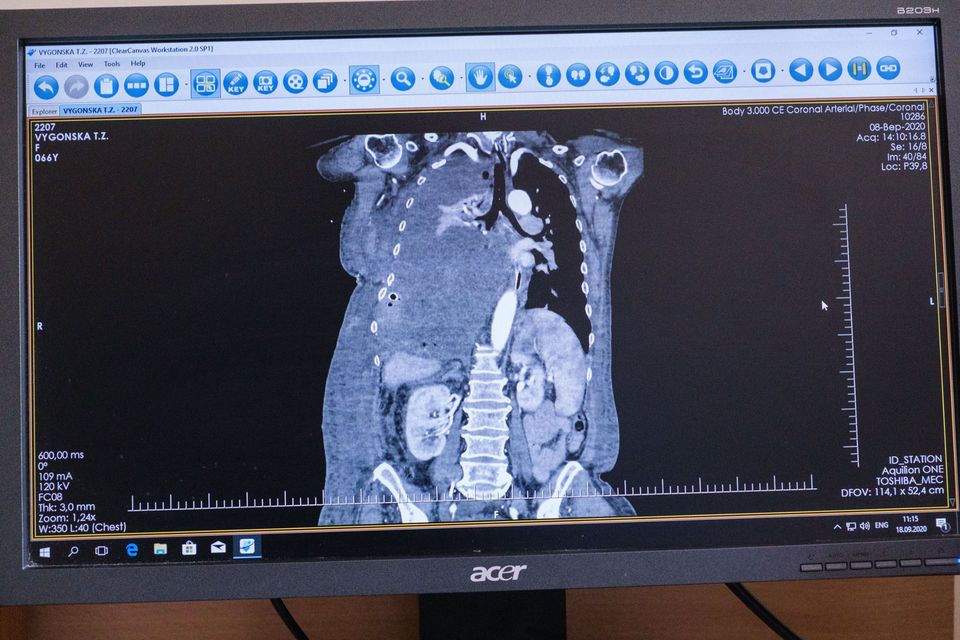

В Киеве в больнице «Феофания» провели уникальную операцию. 66-летнюю пациентку избавили от опухоли, которая разрасталась в груди и весила четыре с половиной килограмма.

О своей болезни жительница Хмельницкой области узнала еще три года назад, но боялась обращаться к врачам из-за нехватки средств. За это время опухоль сильно сдавила правое легкое, не могли нормально работать левое легкое и сердце. В мае текущего года у женщины возникла сильная одышка и общая слабость, а потому пришлось обратиться в больницу в Хмельницком. Там врачи были поражены размером опухоли и перенаправили пациентку коллегам из Киева.

В августе семья приехала в столицу на обследование, а в начале сентября в «Феофании» провели сложнейшую операцию. Хирургическое вмешательство длилось более 12 часов, участвовали свыше 30 специалистов, включая торакального онкохирурга, кардиохургов и кардиоанестезиологов. Об этом сообщает Офис президента, отчитываясь о работе подведомственной больницы.